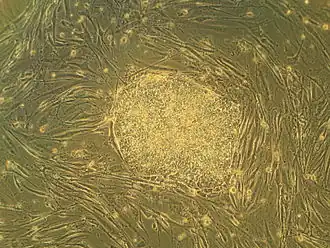

Embryonic stem cells (ESCs) are pluripotent stem cells derived from the inner cell mass of a blastocyst, an early-stage pre-implantation embryo.[1][2] Human embryos reach the blastocyst stage 4–5 days post fertilization, at which time they consist of 50–150 cells. Isolating the inner cell mass (embryoblast) using immunosurgery results in destruction of the blastocyst, a process which raises ethical issues, including whether or not embryos at the pre-implantation stage have the same moral considerations as embryos in the post-implantation stage of development.[3][4]

Embryonic stem cells (ESCs), derived from the blastocyst stage of early mammalian embryos, are distinguished by their ability to differentiate into any embryonic cell type and by their ability to self-renew. It is these traits that makes them valuable in the scientific and medical fields. ESCs have a normal karyotype, maintain high telomerase activity, and exhibit remarkable long-term proliferative potential.[6]

Embryonic stem cells of the inner cell mass are pluripotent, meaning they are able to differentiate to generate primitive ectoderm, which ultimately differentiates during gastrulation into all derivatives of the three primary germ layers: ectoderm, endoderm, and mesoderm. These germ layers generate each of the more than 220 cell types in the adult human body. When provided with the appropriate signals, ESCs initially form precursor cells that in subsequently differentiate into the desired cell types. Pluripotency distinguishes embryonic stem cells from adult stem cells, which are multipotent and can only produce a limited number of cell types.

Under defined conditions, embryonic stem cells are capable of self-renewing indefinitely in an undifferentiated state. Self-renewal conditions must prevent the cells from clumping and maintain an environment that supports an unspecialized state.[7] Typically this is done in the lab with media containing serum and leukemia inhibitory factor or serum-free media supplements with two inhibitory drugs ("2i"), the MEK inhibitor PD03259010 and GSK-3 inhibitor CHIR99021.[8]